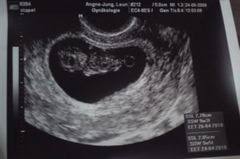

In dieser Woche kommt es bei Deinem Kind zum sogenannten physiologischen Nabelbruch und die Verknorpelung seiner zukünftigen Knochen beginnt. Schwangerschaftswoche der Embryo ist jetzt etwa sechs Wochen alt können Sie im Ultraschall erste Ansätze von Fingern und Zehen sehen. Dies sieht gewiss etwas unförmig aus wirkt aber zuckersüß.

Besonderheiten beim Ultraschall in der 8SSW In der 8Schwangerschaftswoche ist der Kopf noch größer als der gesamte Körper des Embryos. In Ultraschall ist immernoch keine fruchthöhle zu sehen. Das baby ist in der 8 woche 2-3 cm groß und geschlecht wird man sicherlich nicht erkennen können.

Alle inneren Organe sind angelegt und unter dem Gaumen bilden sich die Zahnanlagen. Schwangerschaftswoche ist Ihre erste Vorsorgeuntersuchung fällig. Der Dottersack ist ein wenig beachteter Nebenbefund beim Ultraschall in der Frühschwangerschaft. Bei der ersten von insgesamt 3 Ultraschall-Untersuchungen wird ein Bild des Embryos aufgenommen. Ultraschall beim führenden Marktplatz für Gebrauchtmaschinen kaufe. Er hat jetzt winzige Hände und Füße wobei sich die oberen Extremitäten etwas schneller entwickeln als. Woche ist aus dem mikroskopisch kleinen Zellklümpchen ein 9 bis 16 Millimeter großer Minimensch geworden. Die Ellbogen nehmen Form an und die Entwicklung der Finger beginnt an den Beinen sind Ansätze der Füße und sogar schon Zehen erkennbar. Da meine fa am Anfang der ss in Urlaub war bin ich parallel.